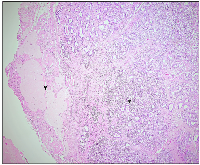

On gross appearance, the right ovary measured 3 × 2 × 1 cm, and on the cut section had a grey-white nodule measuring 1.5 × 1 × 1 cm. The left ovary measured 3 × 1.5 × 1 cm with an unremarkable cut surface. Bilateral fallopian tubes were unremarkable. Microscopically, the right ovary showed a well-delineated tumor composed of tubules separated by fibrous septa. The tumor cells, cuboidal to columnar in shape, exhibited round to oval nuclei with evenly distributed chromatin, focal small nucleoli, and nuclear grooves. Adjacent ovarian tissue was unremarkable. The left ovary and fallopian tubes showed no significant abnormalities, apart from dystrophic calcification in blood vessels (Figures 1 and 2A, 2B). Histopathological findings confirmed a stage Ia pure Sertoli cell tumor (SCT) in the right ovary, with no evidence of malignancy in the left ovary or fallopian tubes. Given the early-stage diagnosis, adjuvant chemotherapy was not required.